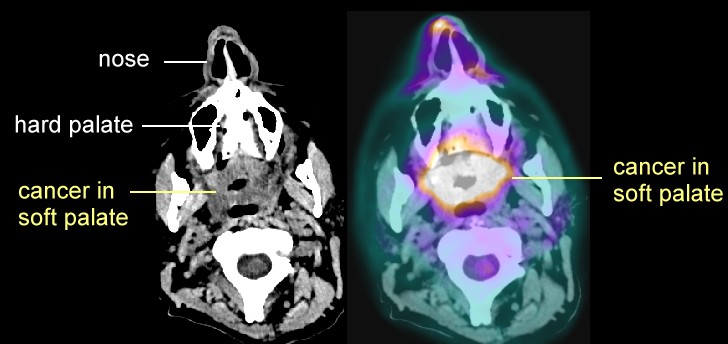

- Soft palate:

PET/CT

here and

here